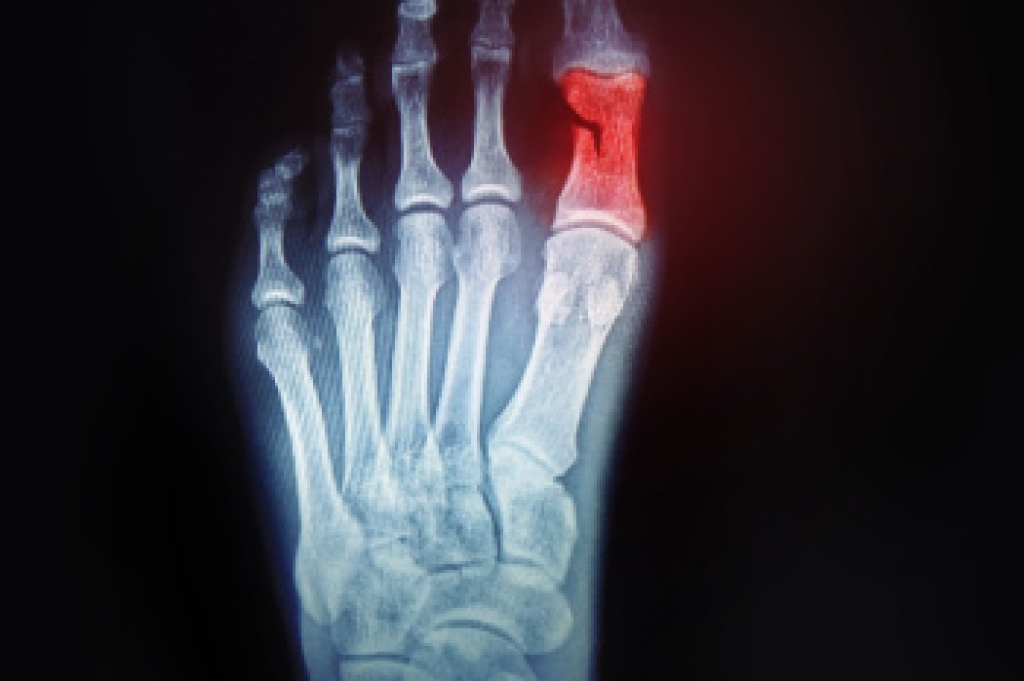

Kohler’s disease - This often targets the bone in the arch of the foot and affects younger boys. It can lead to an interruption of the blood supply which ultimately can lead to bone deterioration. The patient may limp or experience tenderness, swelling, and redness.